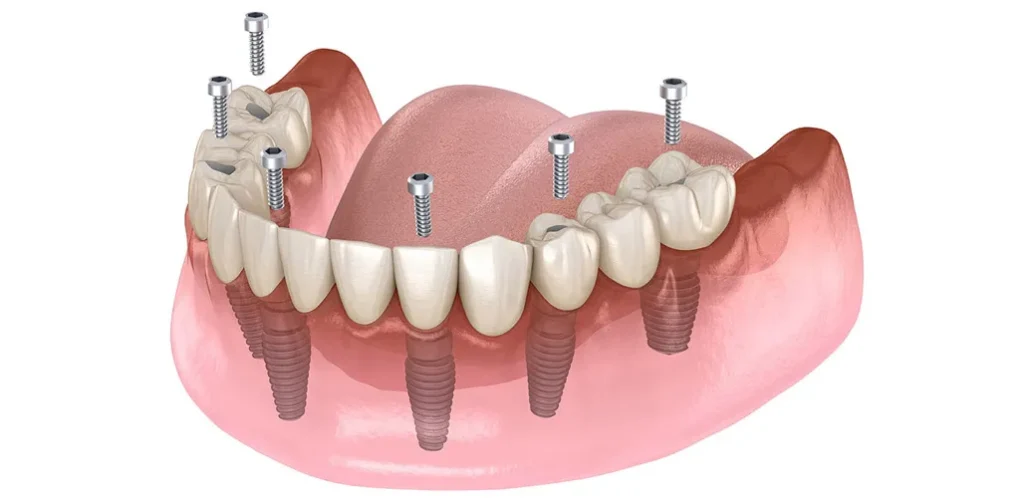

Eksik dişler sadece estetik bir kaygı yaratmaz; aynı zamanda çiğneme fonksiyonlarını bozar ve çene kemiğinde erimeye neden olabilir. İmplantoloji, eksik dişlerin yerine titanyum yapay diş kökleri yerleştirilmesi işlemidir ve en kalıcı çözümdür.

İmplant Tedavisi

Titanyumdan üretilen ve çene kemiğine yerleştirilen bu yapay kökler, üzerine yerleştirilecek porselen dişler için sağlam bir temel oluşturur. Dent360’ta, en güncel teknikler ve biyolojik uyumluluğu en yüksek malzemeler kullanılarak implant uygulamaları yapılmaktadır.

All on Four ve All on Six İmplant

Tamamen dişsiz veya kalan dişleri çekilmesi gereken hastalar için tek bir operasyonda ve tek bir protez ile sabit dişlere kavuşma imkanı sunan yenilikçi çözümlerdir. Hızlı iyileşme ve yüksek konfor sunar.

2. İmplant Tedavisinin Avantajları Nelerdir ve Herkes İçin Uygun mudur?

İmplant tedavisi, eksik dişler için modern tıbbın sunduğu en önemli çözümdür.

Doğal Görünüm ve Hissiyat: İmplantlar, çene kemiğine sabitlendiği için tıpkı doğal dişleriniz gibi görünür ve hissedilir. Çiğneme kuvvetini doğal dişler gibi kemiğe iletir.

Çene Kemiği Korunumu: Diş kaybından sonra kemik erimesi başlar. İmplant, çene kemiğini uyararak erimeyi durdurur ve yüz hatlarının çökmesini önler.

Komşu Dişlerin Korunması: Köprü tedavisinin aksine, implant uygulaması yapılırken komşu dişlerin kesilmesine veya aşındırılmasına gerek kalmaz.

Yüksek Başarı Oranı: Doğru uygulandığında ve ağız hijyenine dikkat edildiğinde, implantların başarı oranı oldukça yüksektir ve ömür boyu kullanım imkanı sunar.

Uygunluk: Genel olarak, yeterli çene kemiği hacmine sahip ve genel sağlık durumu cerrahi operasyon için uygun olan herkese uygulanabilir. Diyabet gibi sistemik hastalıkları olan hastalar, uzman diş hekimi tarafından detaylıca değerlendirilmelidir. Kemik yetersizliği durumlarında ise ileri cerrahi tekniklerle (kemik greftleme) destek sağlanabilir.

2) İmplant mı, köprü mü?

Eksik dişin komşuları sağlıklıysa implant, komşu dişleri kesmeden çözüm sağlar. Köprü; komşu dişlerde büyük dolgular varsa restoratif açıdan mantıklı olabilir. Kemik durumunuza, ağız hijyeninize ve çiğneme alışkanlıklarınıza göre plan yapılır.

3) All-on-Four / All-on-Six bana uygun mu?

Tam dişsizlikte tek aşamada sabit proteze geçiş için iyi seçeneklerdir. Kemik hacmi, sistemik durum, sigara alışkanlığı ve hijyen motivasyonu değerlendirilir. Geçici–kalıcı protez zamanlaması hastaya özelleştirilir.